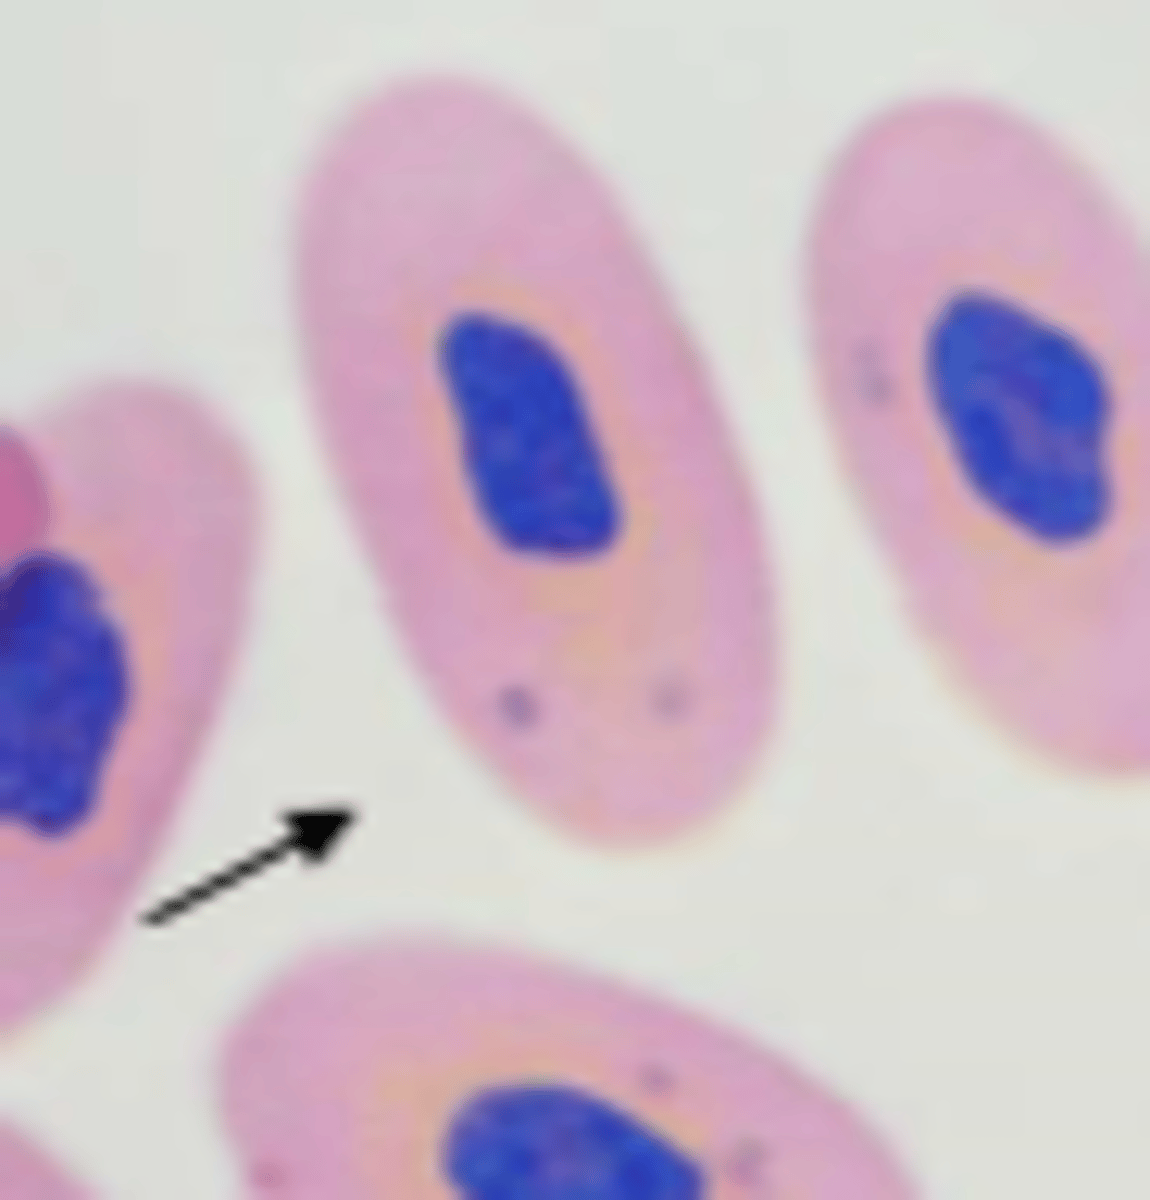

erythrocyte

avian or reptile